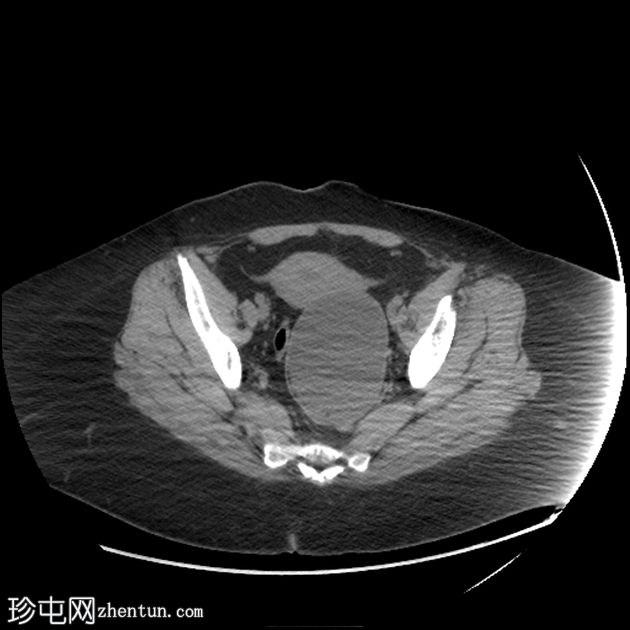

CT

轴位

平扫

可见一主要为囊性肿块,大小为10.1 x 7.3 x 8厘米,囊内含有脂肪球。囊壁可见钙化,并对直肠乙状结肠造成压迫。